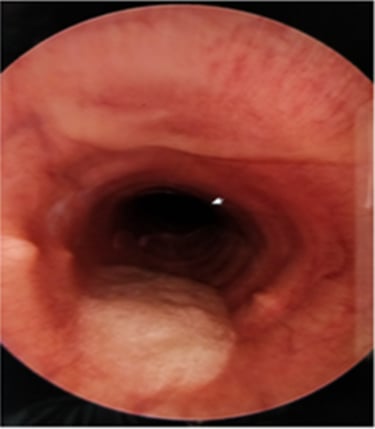

Heeft uw paard last van een aanhoudende of terugkerende hoest? Dan is het aangewezen om een endoscopie (cameraonderzoek) van de luchtwegen te laten uitvoeren. Hoesten wordt namelijk niet altijd veroorzaakt door astma. Tijdens het onderzoek kunnen we ook stalen nemen voor microscopisch en bacteriologisch onderzoek. Op basis van deze resultaten stellen we een behandelplan op maat van uw paard op.

In sommige gevallen is aanvullend een echografie van de longen aangewezen. Dit wordt steeds per situatie beoordeeld en met u besproken.